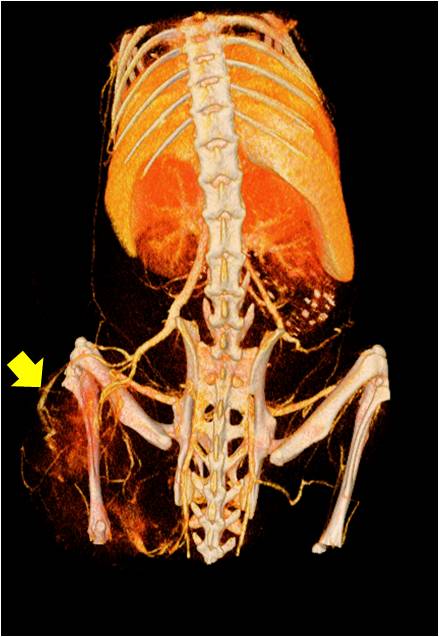

腫瘤血管生成

肺纖維3.jpg

肺轉(zhuǎn)移

小鼠模式,22.5μm像素